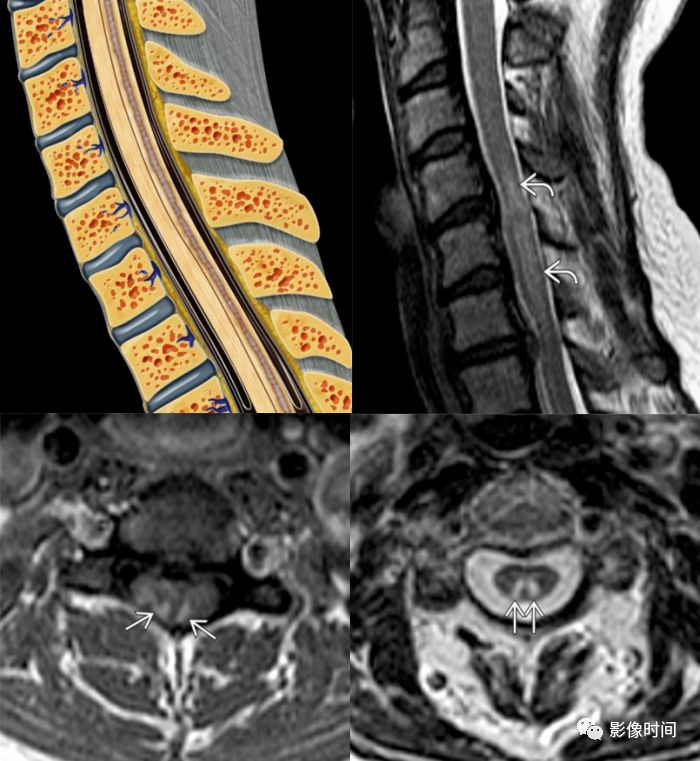

脊髓由灰质和白质组成,颈、胸、腰、骶髓所含灰质和白质的比例并不相同,在横断面上灰、白质的形态和比例也不一样。在脊髓的横断面上,中央为细小的中央管,围绕中央管周围的是「H」形的灰质,灰质的外面是白质。

T2WI显示脊髓内长节段高信号,范围超过脊髓直径2/3,斑片状明显强化

T2WI显示脊髓内长节段高信号,增强扫描出现多发结节状高信号,位于脊髓表面

T2WI双侧灰质前角对称结节状高信号,似「鹰眼」